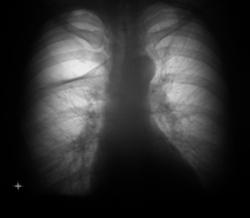

При расшифровке цифровых флюорограмм задумался.

Сложилось впечатление, что имеет место ателектаз верхней доли справа. Посмотрели имеющийся архив за 2007, 2008 годы.

ВАШЕ МНЕНИЕ УВАЖАЕМЫЕ КОЛЛЕГИ?

Ух, если предшествовало падение с летнице , возможно как следствие ограниченный пневмоторакс.

На буллу не похоже, картина ограниченного пневмоторакса.

Действительно не обычно смотрится. При ограниченном пневмотораксе границы обычно вогнутые, а не выпуклые, но другого варианта у меня тоже нет - локальный пневмоторакс.